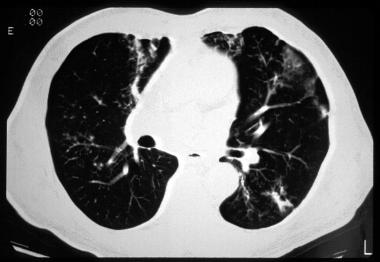

图10 可见支气管周围的磨玻璃样浑浊及过度充气

图片

图11 CF及急性胸痛患者的CT显示柱状型及囊状性支气管扩张,以及右上叶的空隙和皮下气肿。气胸是出现囊肿时的常见并发症。